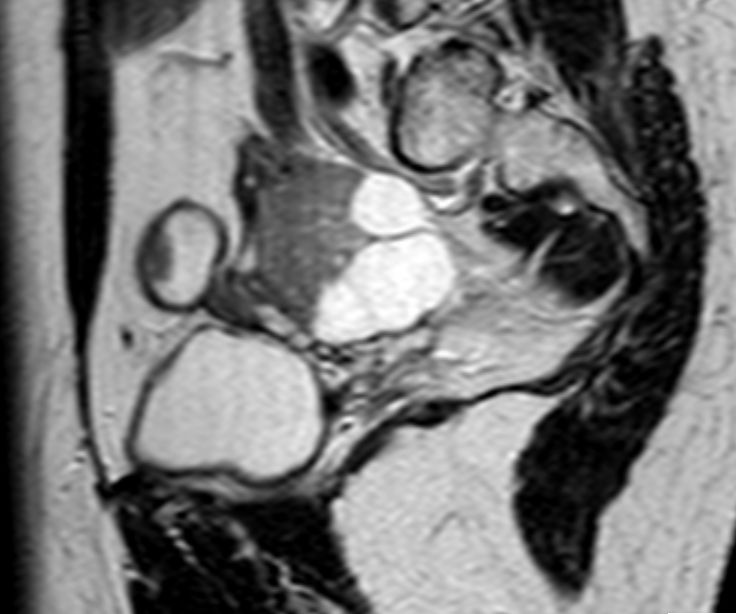

73-jährige Frau mit Ascites, Pleuraerguss links und Unterbauchtumor.  Das Netz ist komplett in einen Omental-Cake umgewandelt. An der Zwerchfellkuppe miliare Tumoraussaat.

Beide Adnexe in knapp kindskopfgroße blumenkohlartige Tumoren umgewandelt.

Im Douglas finden sich pararektal mehrere bis zu pflaumengroße Tumorknoten.